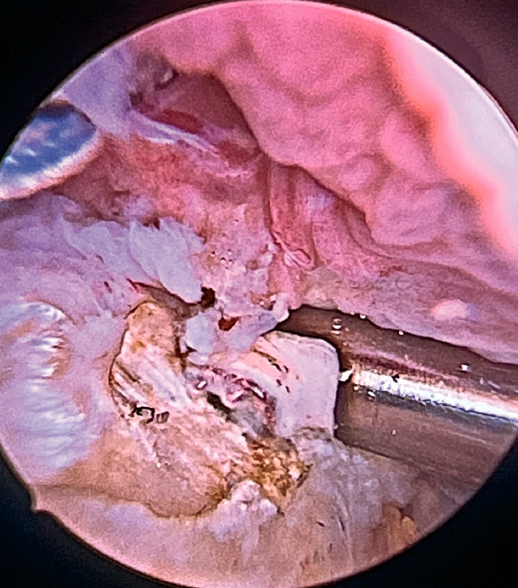

Having passed both the anterior and the posterior sutures, we proceed to knot, through the lateral portal with a working cannula, each of the sutures, starting posterior and ending anterior.

Finally, the anterolateral supraspinatus threads are used in combination with the posterolateral tapes to establish a more lateral double row with two direct anchorings that allow the threads to be threaded through two loops(Biocomposite SwiveLock® C 4.75 × 19.1 mm, Arthrex, Naples, FL, USA). This achieves a tension-free double row repair of the supraspinatus, covering the superior capsular repair made with the LPB (Figure 11).

Once suturing is complete, the arthroscope can be reinserted into the glenohumeral joint to check the final result of the superior capsular reconstruction with the LPB and, especially, the correct repair of the supraspinatus to its footprint on the greater tuberosity (Figure 12).